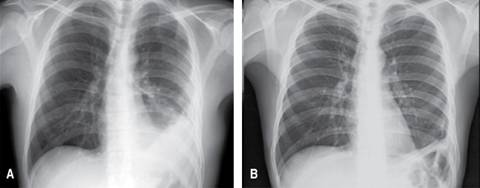

Paciente de sexo masculino de 31 años, referido de centro hospitalario de primer nivel por cuadro de dificultad respiratoria súbita secundaria a hemotórax izquierdo, sin antecedente previo de trauma, el cual fue manejado con sonda pleural con gasto de 1,500 cc al momento de la colocación y enviado a centro hospitalario de tercer nivel para continuar manejo. En la radiografía de tórax inicial se observa una imagen sugestiva de fondo gástrico en el interior de la cavidad torácica izquierda (Figura 1) y debido a que sus signos vitales eran normales, se decidió hacer TC toracoabdominal con doble contraste, en el que se confirma sospecha de hernia diafragmática izquierda, la cual contenía en su interior estómago y grasa mesentérica (Figuras 2 y 3). Se realizó abordaje abdominal línea media, se detectó defecto diafragmático de 3 cm de diámetro, posterolateral izquierdo con contenido no reductible, por lo que fue necesaria la ampliación del defecto; encontrando epiplón y estómago en su interior, este último con paredes isquémicas, zonas necróticas y una perforación de 4 cm de diámetro a nivel de la curvatura mayor (Figura 4), razón por la que se realizó gastrectomía total con anastomosis esófago-yeyunal y reconstrucción en Y de Roux. En el postoperatorio fue trasladado a la unidad de terapia intermedia con apoyo ventilatorio por un periodo de cinco días, además se empleó nutrición parenteral total durante siete días. El quinto día fue valorado por neumología por hallazgos radiográficos de inadecuada expansión pulmonar posterior al evento quirúrgico (Figura 5), refiriéndose la presencia de hipoplasia pulmonar con derrame pleural compensatorio, confirmando la sospecha diagnóstica de hernia de Bochdalek. Fue egresado asintomático 17 días posteriores al procedimiento. El seguimiento actual es de dos años, actualmente se encuentra asintomático, las radiografías de tórax de control sin alteraciones (Figuras 6A y 6B) así como función respiratoria normal.

Figura 6: Radiografía AP tomada como seguimiento a los seis meses (A) y 24 meses (B) por parte de consulta externa de cirugía en la que se observa discreta disminución del volumen del hemitórax izquierdo (A) en comparación con su contralateral (B) así como derrame pleural residual que posteriormente desaparece, dando como resultado elevación de cúpula diafragmática izquierda por proceso esperado de retracción.